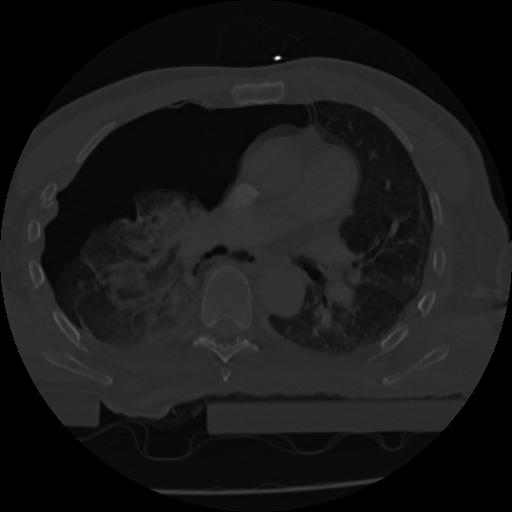

22 ANGIO,CE,Vol,0.5,ANGIO,,